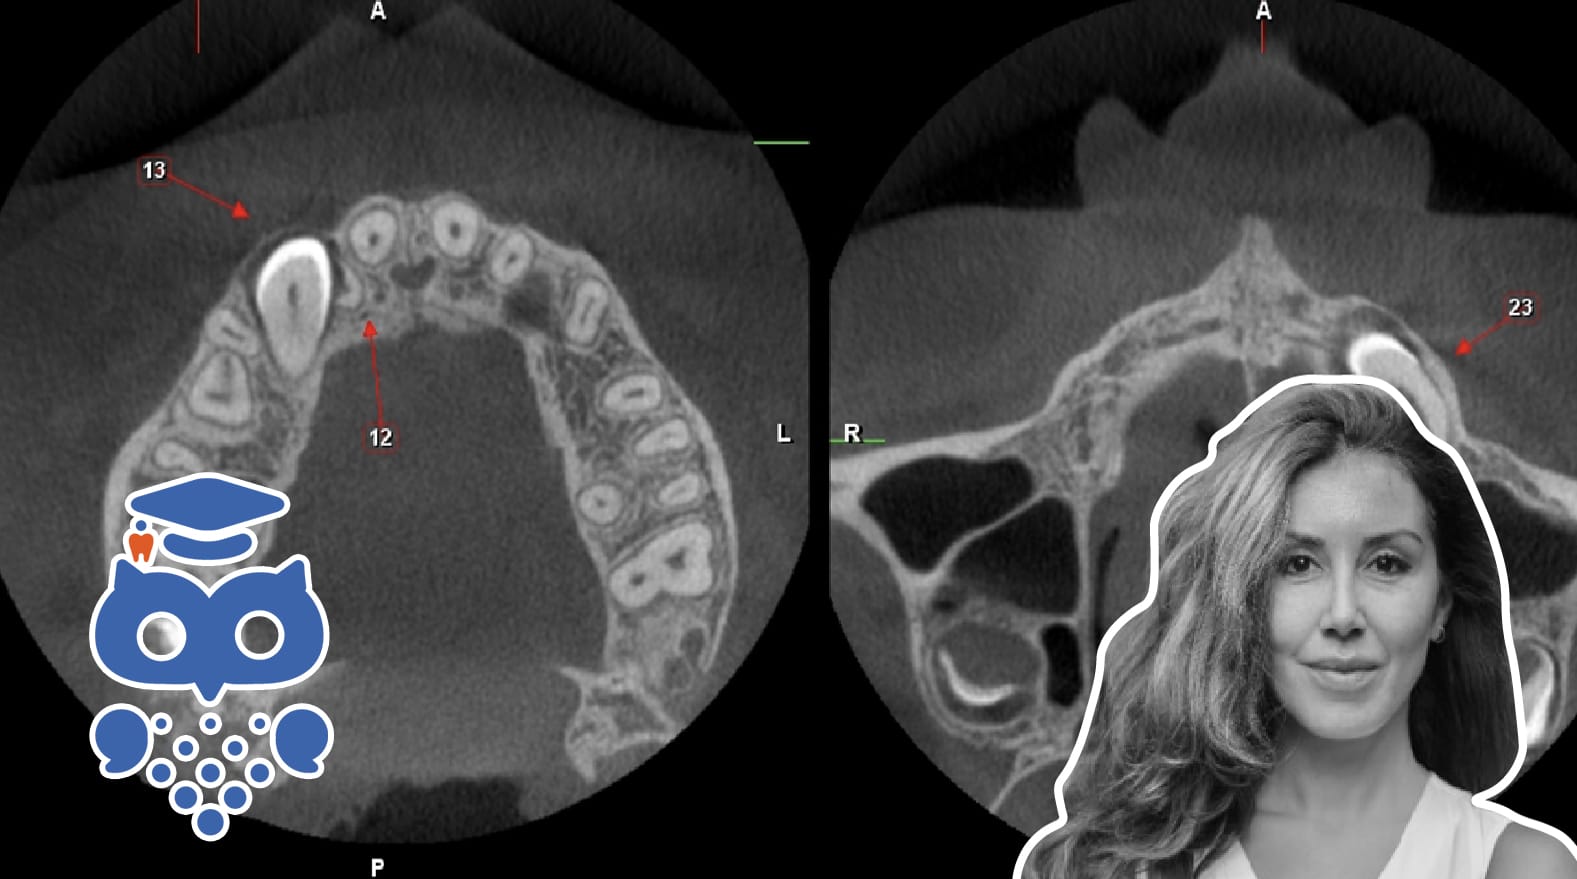

Röntgenundersökningar för implantatbehandling följer ALARA-principen för att minimera stråldoser. Panoramaröntgen och intraorala bilder används för översikt och detaljer. Vid behov av 3D-data används CBCT, som ger hög upplösning och lägre doser än medicinsk CT. Stråldos styrs av FOV-storlek.

Röntgenundersökningar som utförs i samband med implantatbehandling har olika omfattning beroende på om det gäller planering eller uppföljning av behandling. Vid planering av behandling har det också betydelse var i käkarna  de tandlösa partierna finns och var implantatbehandling kan vara aktuell. Det finns ett flertal olika röntgenapparater som kan användas  för röntgenundersökning i samband med implantatbehandling och röntgenbilder från de olika apparatur ger information i varierande omfattning.